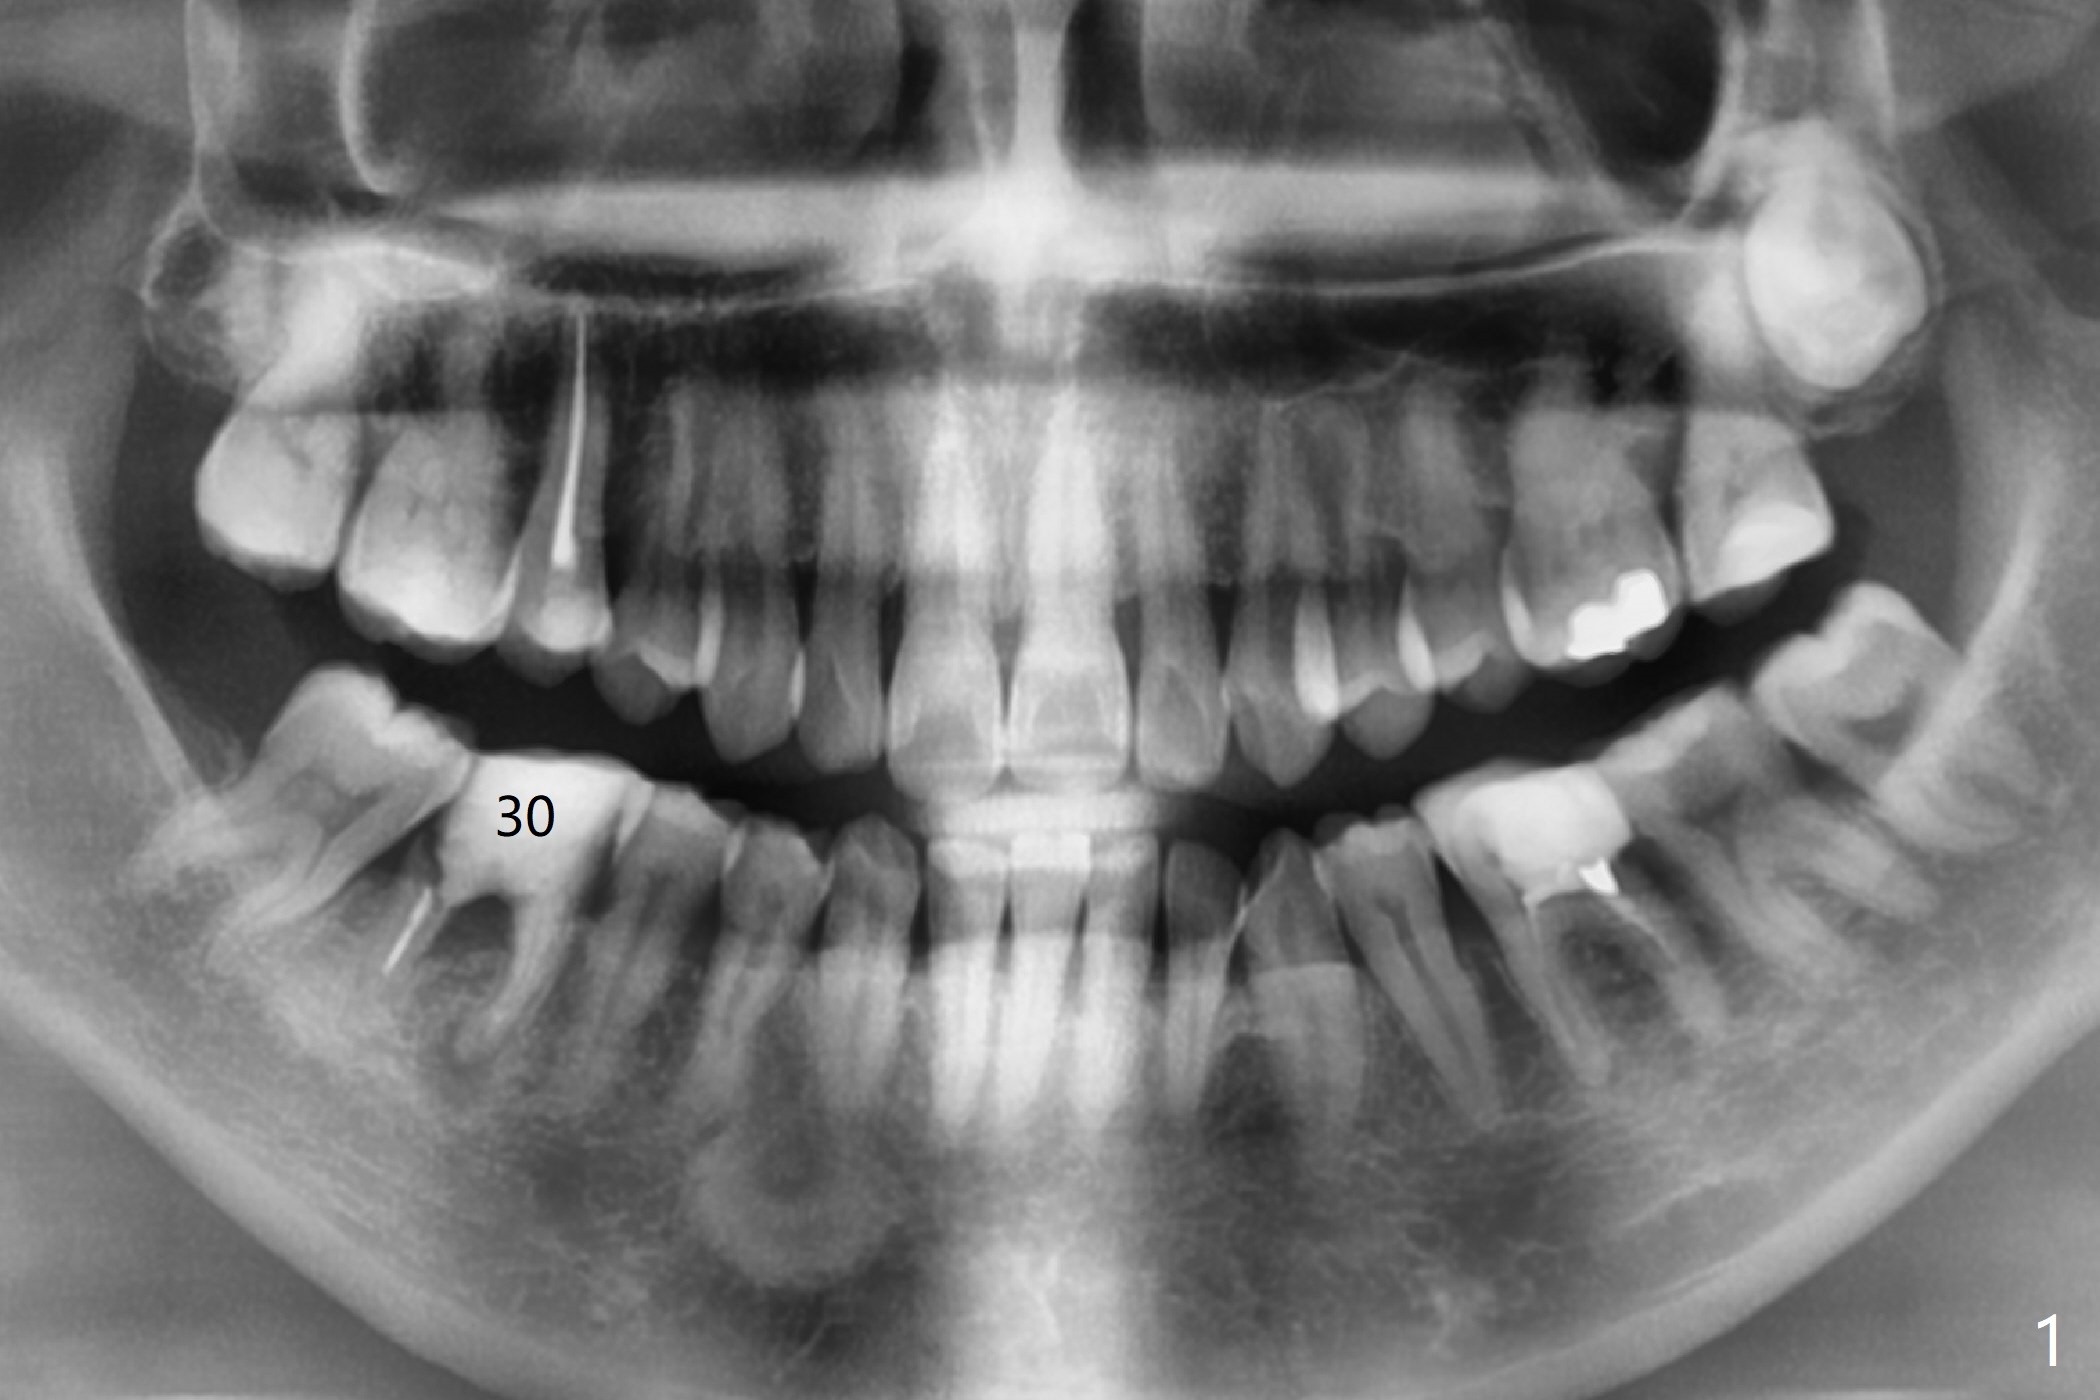

A 48-year-old woman has chewing pain at #30 with distal root fracture and a large mesial apical lesion (Fig.1). To reduce abutment screw loosening, guided surgery is planned with implant placed at the crestal level (Fig.2 <). Because of the large apical lesion, a longer implant (11.5 mm) will be placed than that Fig.2 indicates.